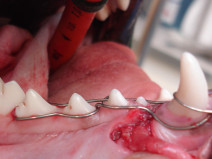

• Soirée Dentisterie : gestion des traumatismes de la face

Dernier volet de notre trilogie sur la dentisterie, le Dr Florian Boutoille nous apprendra ici les bonnes pratiques afin de gérer les traumatismes dentaires : symphyse mandibulaire, fractures mandibulaire ou maxillaire, articulation temporo-mandibulaire, fente palatine ; cerclage, plaques vissées et résines n'auront plus de secret à l'issue de cette présentation !